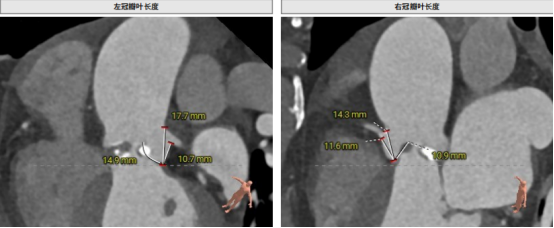

CT結(jié)構(gòu)評估

患者為功能性二葉瓣,瓣葉增厚,輕度鈣化,鈣化主要集中在左竇瓣葉上,左冠脈高度較低,結(jié)合瓣葉長度,竇部結(jié)構(gòu)綜合評估左冠風(fēng)險較低,但左冠瓣葉瓣尖處有鈣化團塊,在球擴以及瓣膜釋放時仍需注意左冠灌注情況,由于鈣化團塊位置特殊,建議做冠脈保護處理,右側(cè)股動脈作為主入路,穿刺點位于股骨頭中段即可。